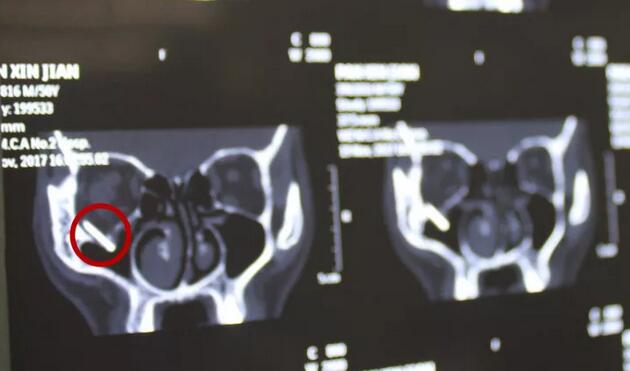

上周一,刘先生骑电动车回家时,在路上遇上车祸,在当地医院,刘叔叔进行了初步的清创缝合处理后。拍了头部的CT才发现刘先生眼眶内竟然有一块类似铁片的巨大异物!

福州眼科医院李谦益主任接诊后,经过详细检查后发现:刘先生虽然眼部周围的外伤已经基本缝合,但是CT显示眼眶内存留的异物巨大,情况比较紧急。李谦益主任随即组织福州眼科医院眼眶病科里医疗团队,进行多次会诊讨论病情后制定了手术医治方案。在11月21日下午,为刘先生施行了眼眶内异物取出的手术,因为前期的详尽准备,手术不到一小时就顺利完成,李谦益主任不仅为刘叔叔顺利取出了巨大异物(玻璃板),还为其保住了视力与光明。